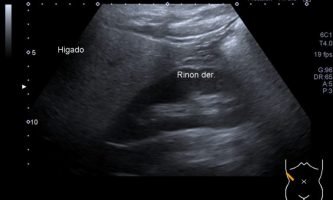

El médico de referencia le indica nueva ecografía de control, donde se observan múltiples y extensas lesiones focales hepáticas hiperecogénicas, redondeadas y confluentes, las cuales predominan en adyacencia a venas supra hepáticas, sin condicionar efecto de masa y sin alteración de la superficie hepática(fig. 1 y 2). Ante la valoración con Doppler color no presenta patrón de flujo peri ni intralesional y respeta el calibre de las venas supra hepáticas(fig. 3 y 4). Dada las características ecográficas se sospecha esteatosis focal multinodular confluente como principal diagnóstico presuntivo, siendo los diagnósticos diferenciales patologías de naturaleza infecciosa, tumoral o metastásica.

El examen radiológico abdominal más comúnmente utilizado en prevención es la ecografía (US) dado que es un método económico y accesible, no invasivo y que no utiliza rayos X, con el cual se logra fácilmente el diagnóstico de esteatosis, dado que se reconoce aumento difuso de ecogenicidad del parénquima hepático. Los criterios principales: la ecogenicidad del parénquima hepático debe ser mayor que la de la corteza renal, mala definición diafragmática, de los vasos supra hepáticos y de la arquitectura intra hepática.2(fig. 8, 9a y 9b)